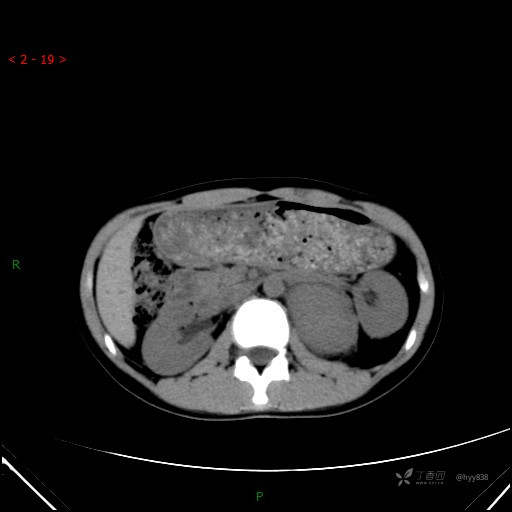

CT值